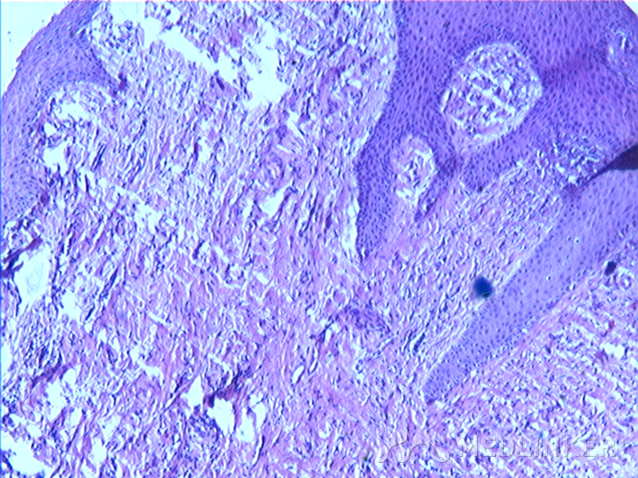

组织病理:角化过度,表皮增生,真皮乳头可见胶原增生与表皮排列垂直分布,真皮浅层血管周围少量炎细胞浸润。

讨论:获得性甲周纤维角化瘤临床表现,一般肿物长轴与侧甲沟走行一致,顶部角化,质硬,损害下甲板形成纵行凹陷.组织病理学活检提示:表皮角化过度,棘层肥厚,真皮可见大量增生的胶原纤维及成纤维细胞,增生胶原排列与表皮垂直分布。获得性甲周纤维角化瘤根据特征性临床表现及组织病理易被诊断,治疗以保留甲母质的外科手术切除为佳。需要与结节性硬化的甲周纤维瘤相区别。